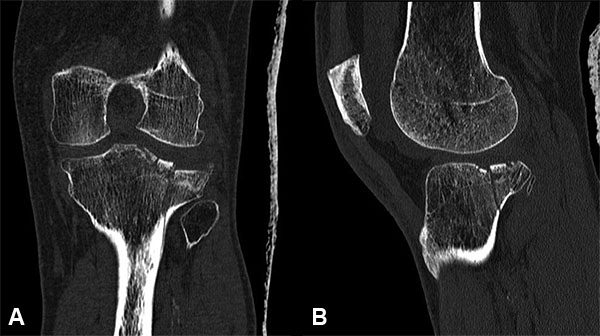

El diagnóstico se realizó siguiendo los hallazgos clínicos, radiográficos, de la tomografía computada o la RMN según el caso (figs. 1 a 7).

Figura 4: Masculino 58 años. Schatzker V.

Figura 5: Masculino 58 años. Schatzker V.

Figura 6: Cortes tomográficos paciente anterior.

Figura 7: Reconstruccion TAC 3D.